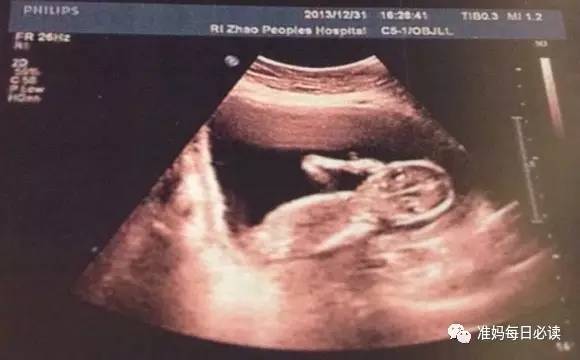

既然胎头脸朝上造成难产的机会很大,那么是否可于待产时靠超声波扫描来避免这段冤枉的产程,直接选择剖腹产呢?这种方法也不尽然可行。

因为宝宝的头会旋转,待产时胎头的方向未必相同于子宫颈全开时的状况;此外,有可能胎头已深入产道,腹部超声波根本无法扫描得到,若转而改用阴道超声波,除非能清楚看到宝宝的眼眶或口鼻部位,再来猜测胎儿的方位,或许才有诊断的价值。